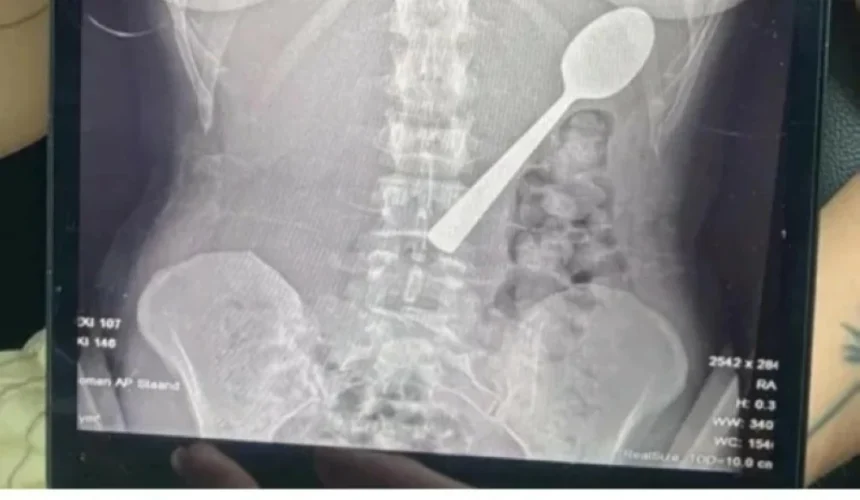

وبعد مراجعة الأطباء، جاءت الصدمة الثانية: فالملعقة أكبر من أن تمر عبر الجهاز الهضمي طبيعياً، ولا بد من تدخل طبي عاجل. وبعد انتظار يومين تحت المراقبة، خضعت ريمي لعملية منظار معدة تحت التخدير الموضعي، اضطر خلالها الأطباء إلى تدوير الملعقة بعناية داخل المعدة لسحبها، ما تسبب في نزيف طفيف والتهاب مؤقت في الحلق.

After consulting doctors, the second shock came: the spoon was too large to pass through the digestive system naturally, and urgent medical intervention was necessary. After waiting two days under observation, Remy underwent a gastroscopy under local anesthesia, during which the doctors had to carefully rotate the spoon inside her stomach to extract it, causing slight bleeding and temporary throat inflammation.